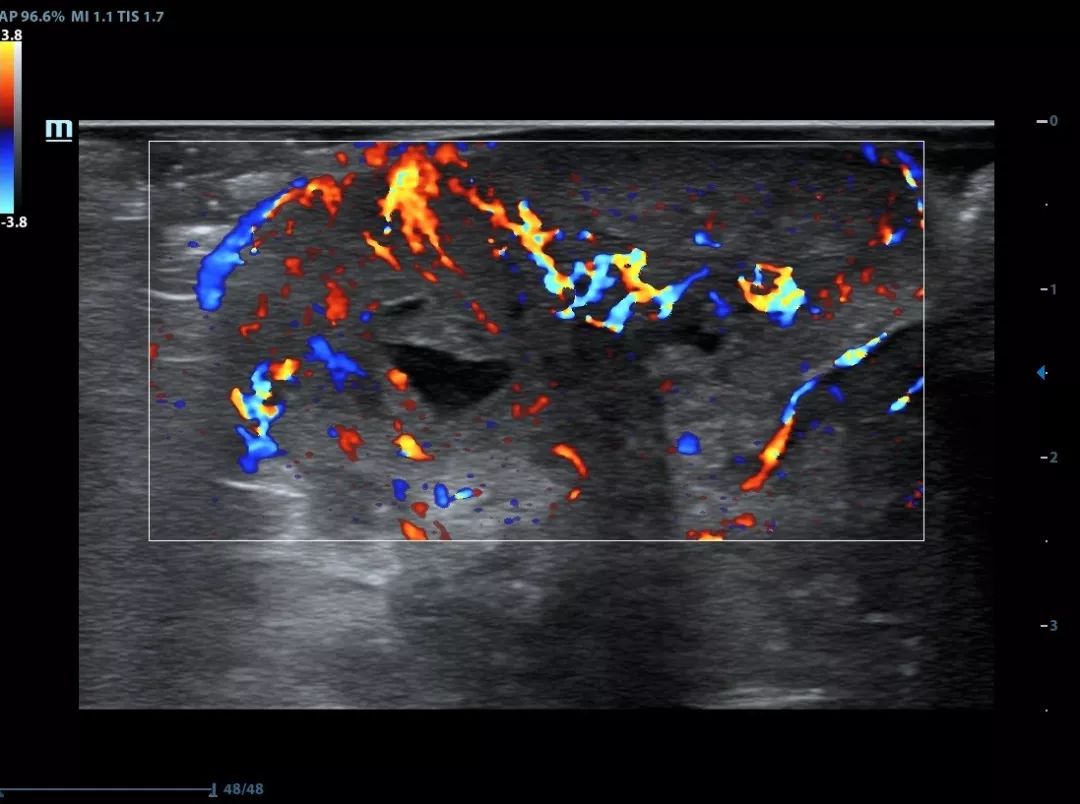

ComboWave Transducer Technology

X-Insight provides ComboWave linear transducers for thyroid, breast, vascular and other applications. The transducers utilize a new type of composite piezoelectric material to dramatically optimize the acoustic spectrum and reduce acoustic impedance, allowing clinical experts to experience outstanding performance with extreme image resolution and uniformity.

HR flow of breast tumor

Nodular goiter